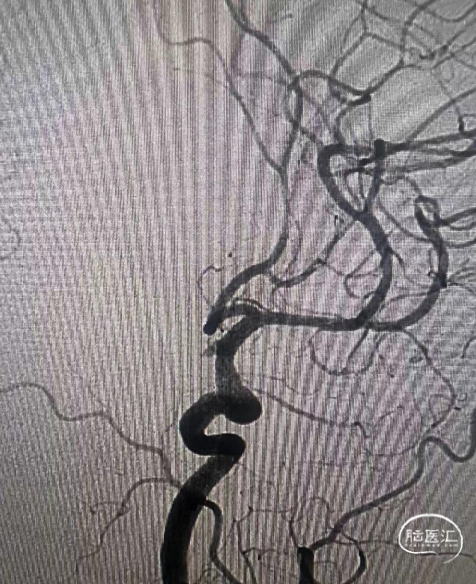

术前造影:

通桥麒麟™血流导向密网支架释放即刻造影:贴合良好,瘤腔内明显血液滞留。